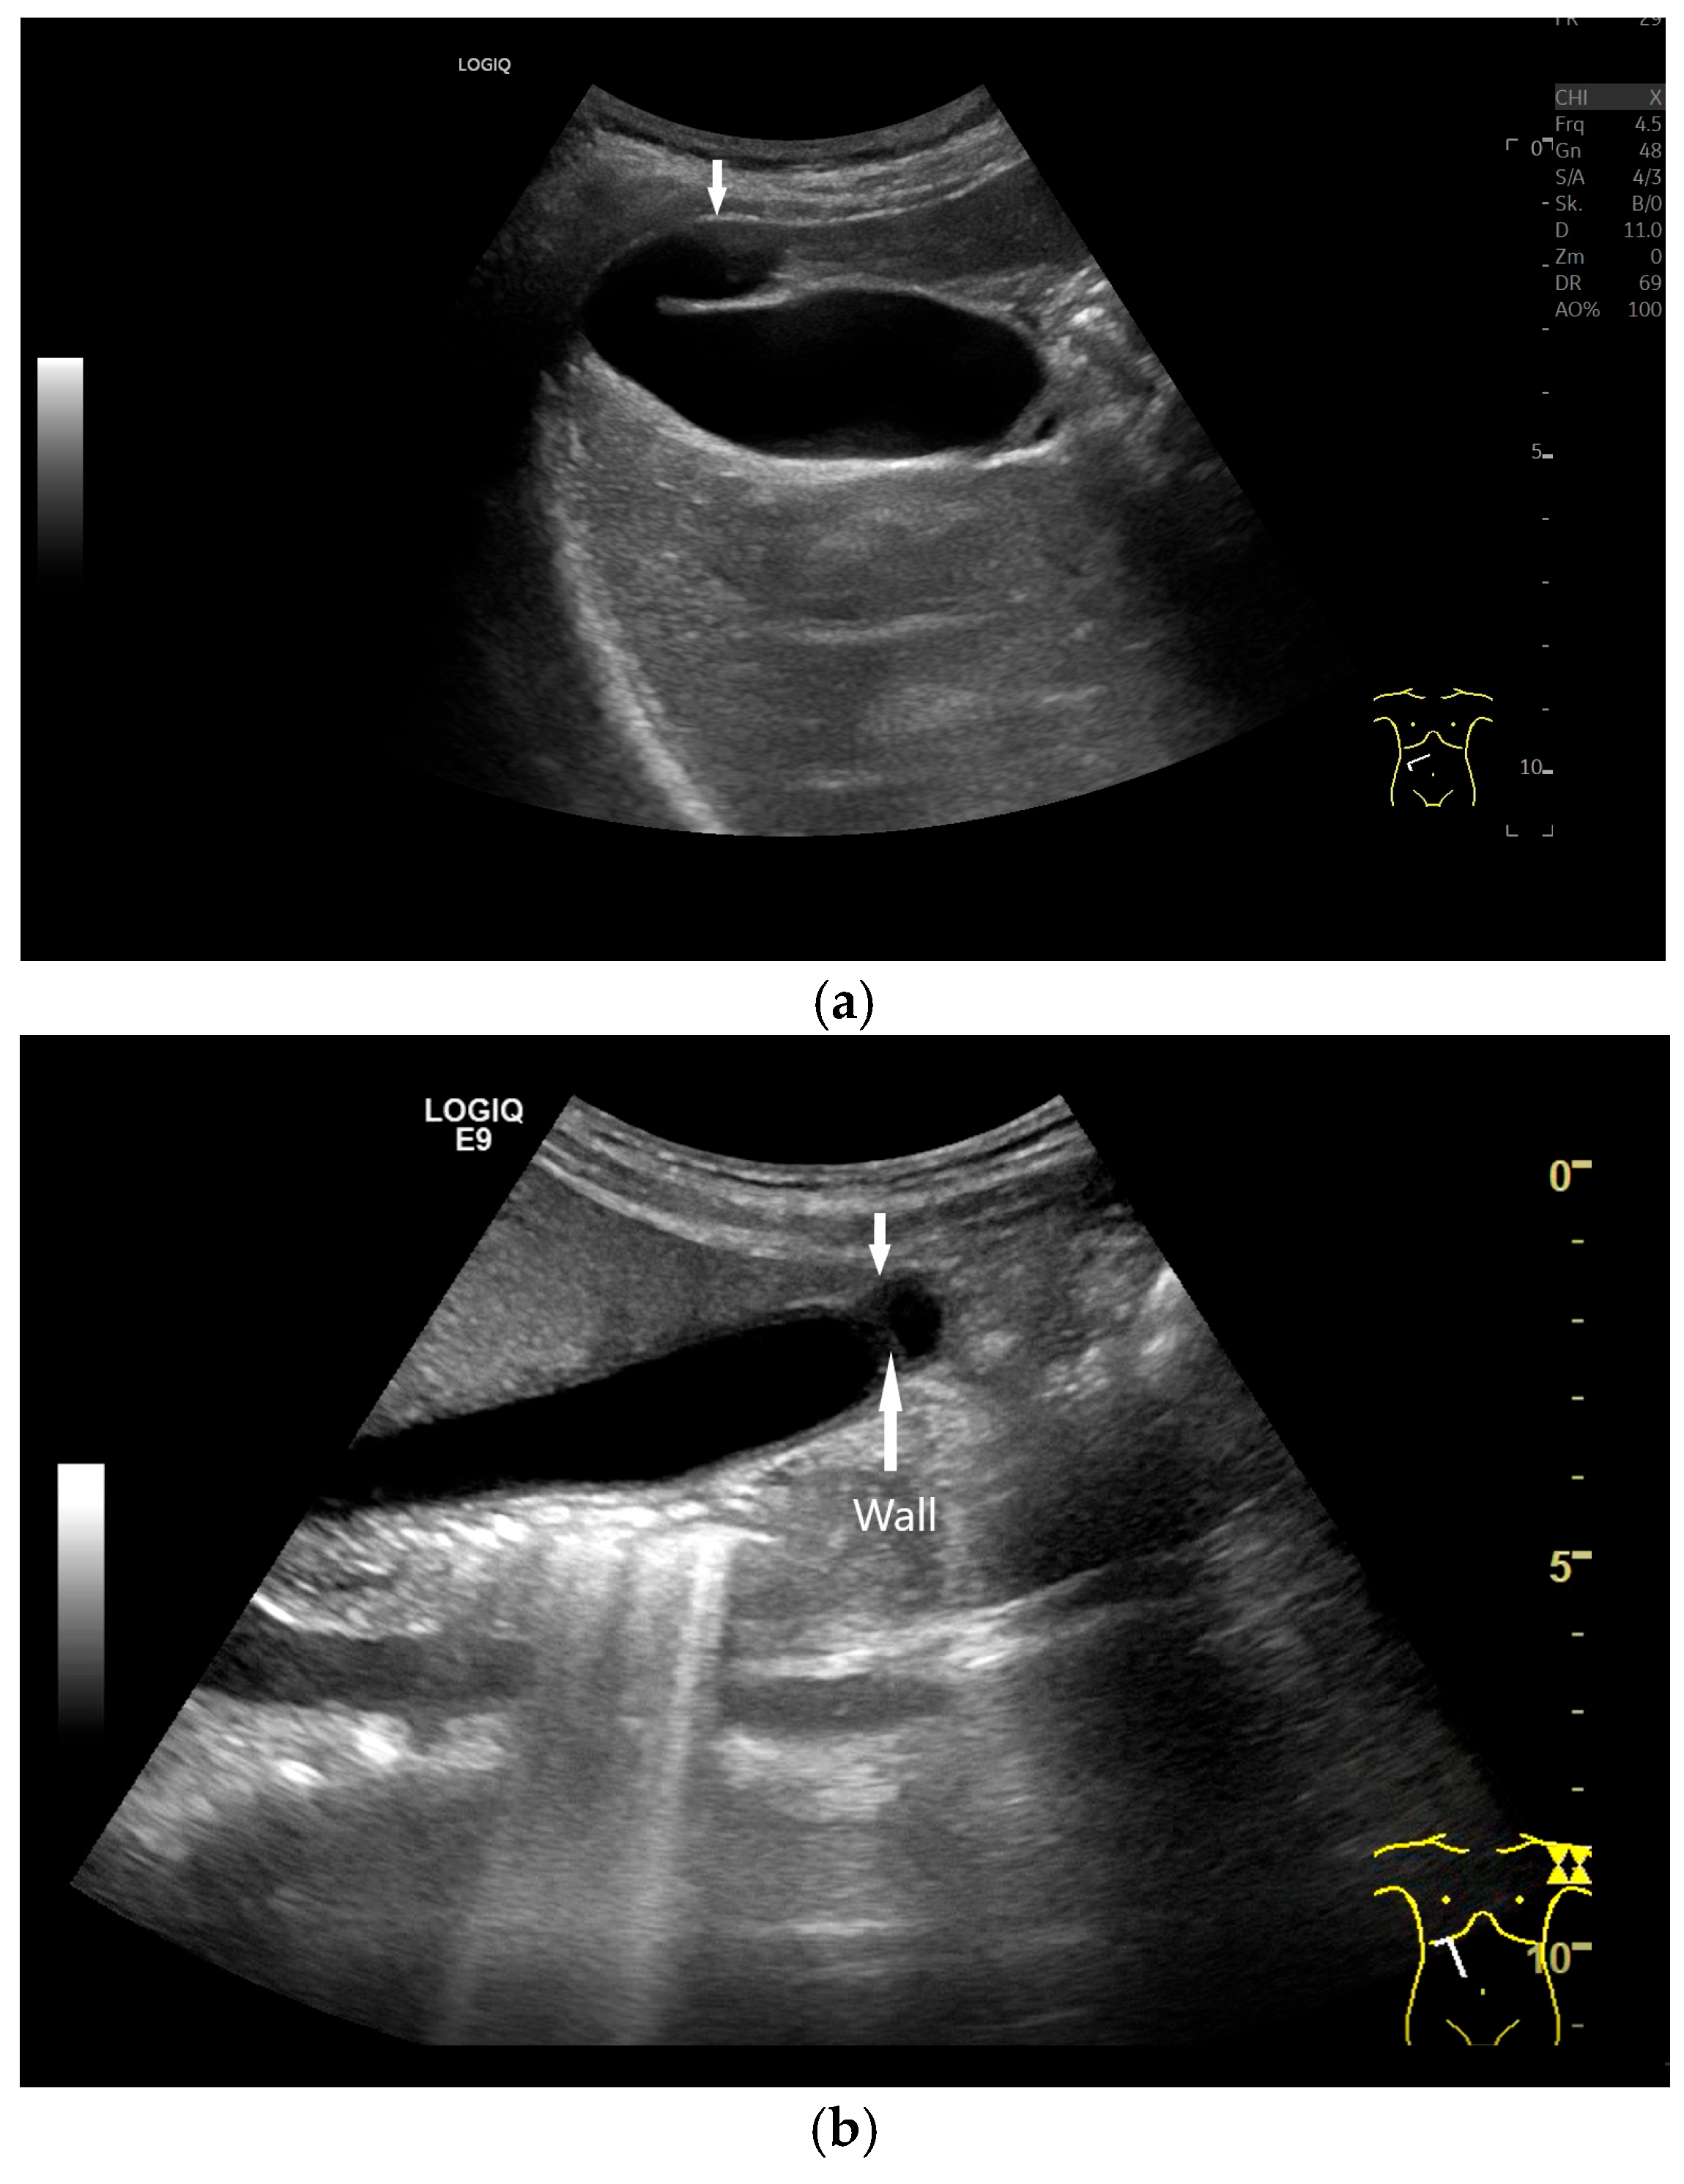

3.3. Gallbladder Wall

4.1. Diffuse Gallbladder Wall Thickening

- Vriesman, A.C.v.B.; Engelbrecht, M.R.; Smithuis, R.H.M.; Puylaert, J.B.C.M. Diffuse gallbladder wall thickening: Differential diagnosis. Am. J. Roentgenol. 2007, 188, 495–501. [Google Scholar] [CrossRef]